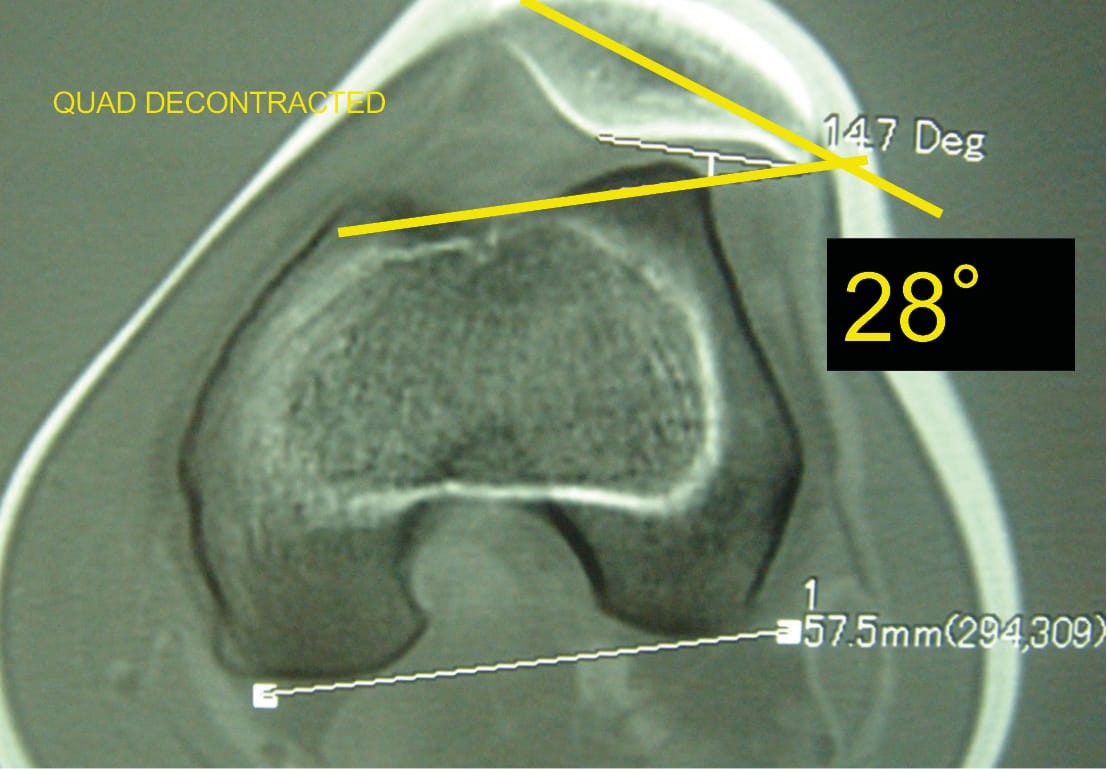

The third factor retained in 1987 was patellar tilt.

Patellar tilt is the expression of malalignment of the patella in the horizontal plane. Patellar tilt depends on bone anatomy but also on the retinacula or patellar ligaments and the quadriceps muscle.

The presence of patellar tilt greater than 20° with relaxed quadriceps was found in 83% of patients belonging to the objective patellar instability group. This tilt was initially attributed to VMO dysplasia. Our subsequent work showed that trochlear dysplasia, patellar height, and the TT-TG value evidently influenced patellar tilt.

On a trochlear section passing through the Roman arch, the patellar tilt, which is the angle formed by a line passing through the long axis of the patella and the tangent to the posterior condyles, is, here, 28° with relaxed quadriceps (Figure 30).